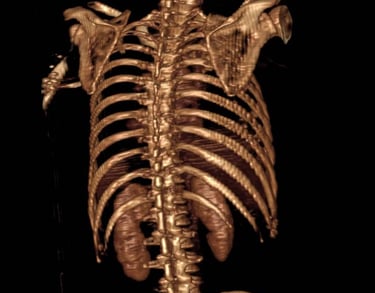

Atención médica integral para problemas de columna vertebral cervical, torácica y lumbar.

Padecimientos que atendemos.

Enfermedades de la columna vertebral.

Columna cervical

Columna torácica.